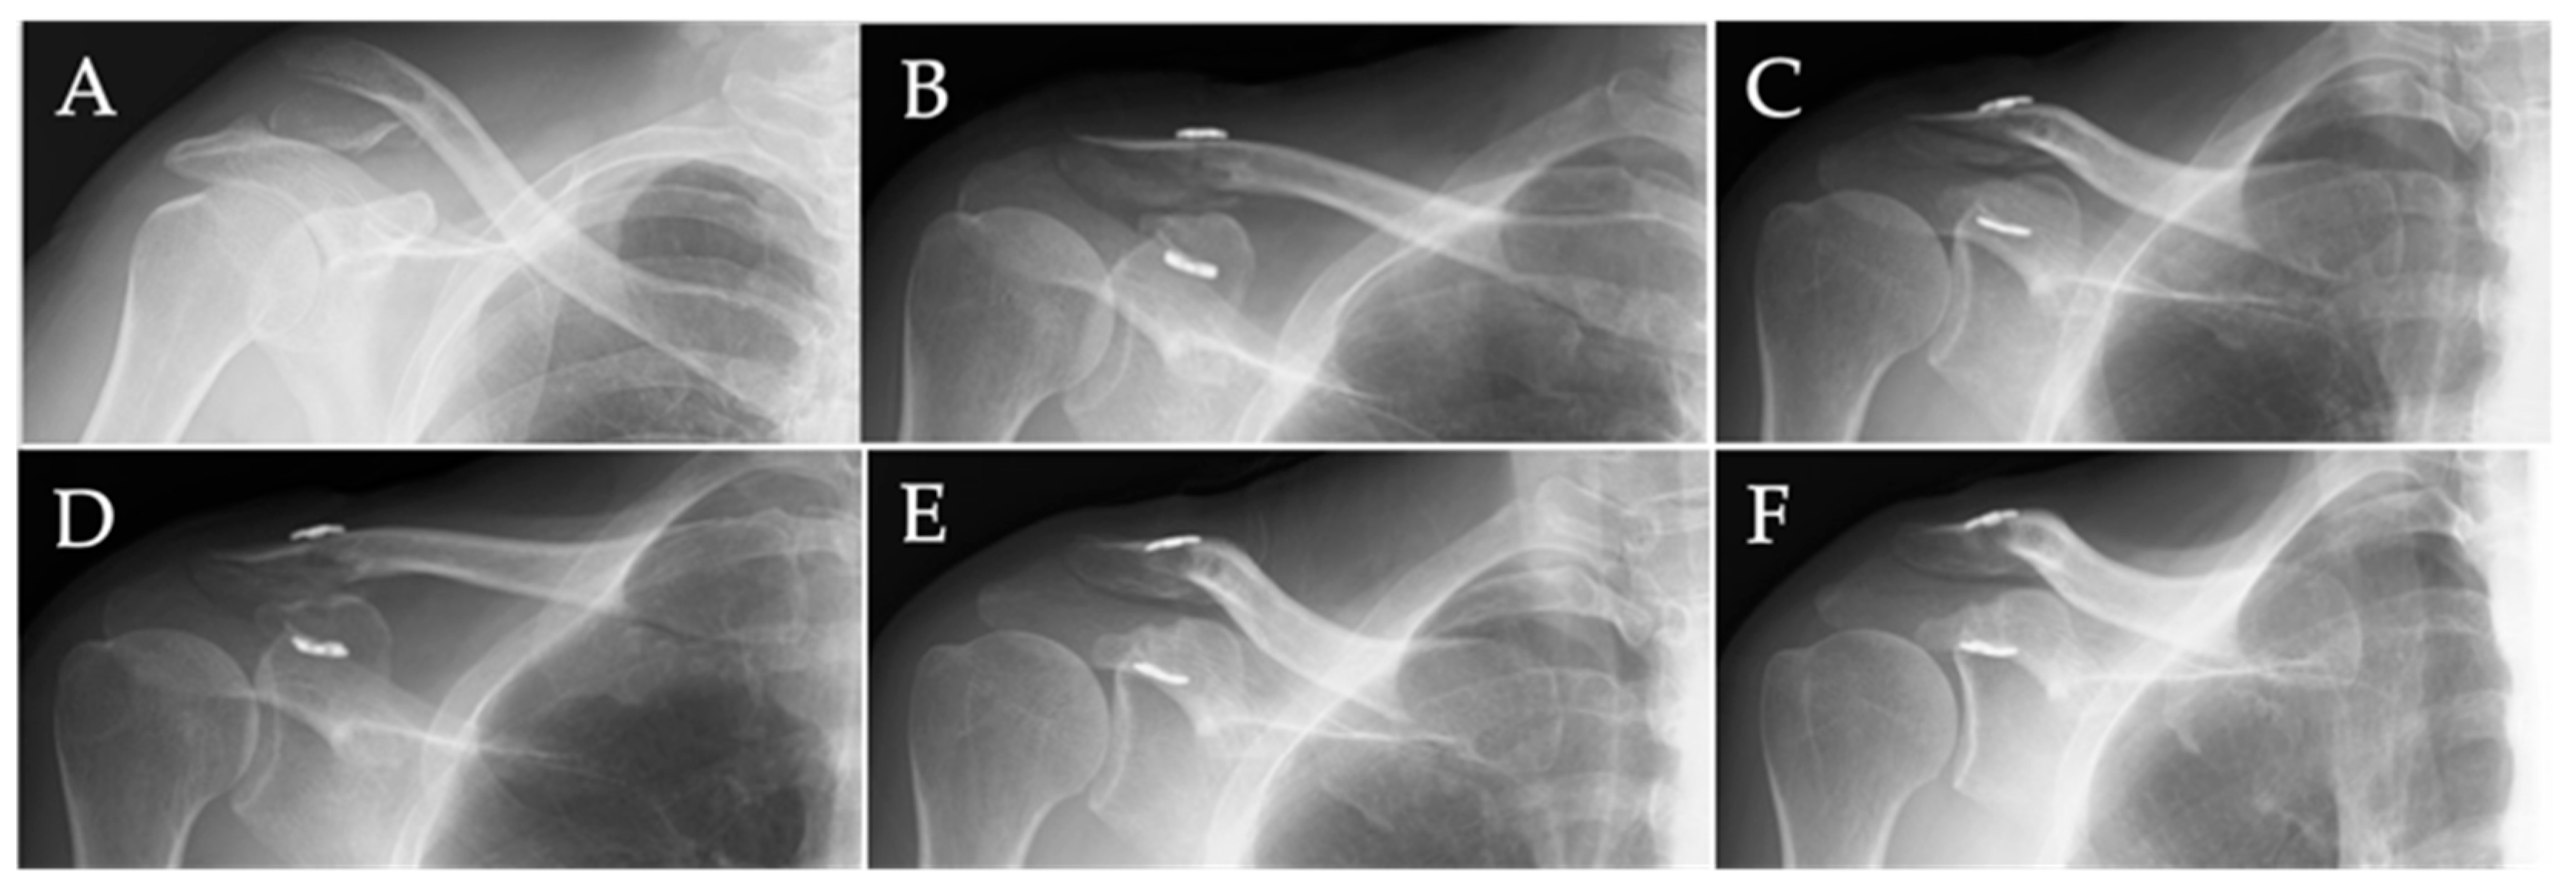

3.2. Radiological Analysis